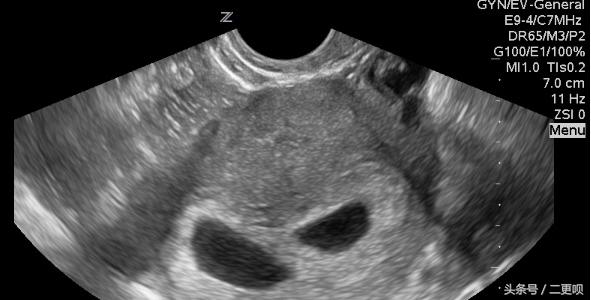

附上当时孕7周的B超单

孕7周B超单

在孕7周的时候由于内分泌流了点粉色的东西,加上肚子偶尔有点疼,不放心就去医院检查。B超照到显示有一胎囊,心管脉动等一切都正常,给我打了三天的黄体酮,后来一切正常。